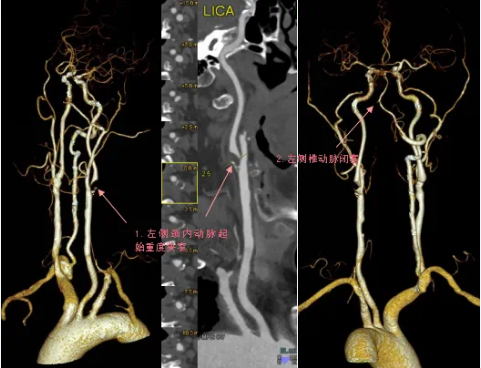

70岁的程爷爷,突然出现右侧肢体无力,右上肢勉强抬举,右下肢不能撑重,还有口角歪斜症状,到河北省第八人民医院(河北省老年病医院)就诊检查,医生了解病情后,随即为老人开具了头颈部CTA检查,检查结果显示程爷爷的左侧颈内动脉起始部重度狭窄,几近闭塞;左侧椎动脉重度狭窄,局部闭塞。